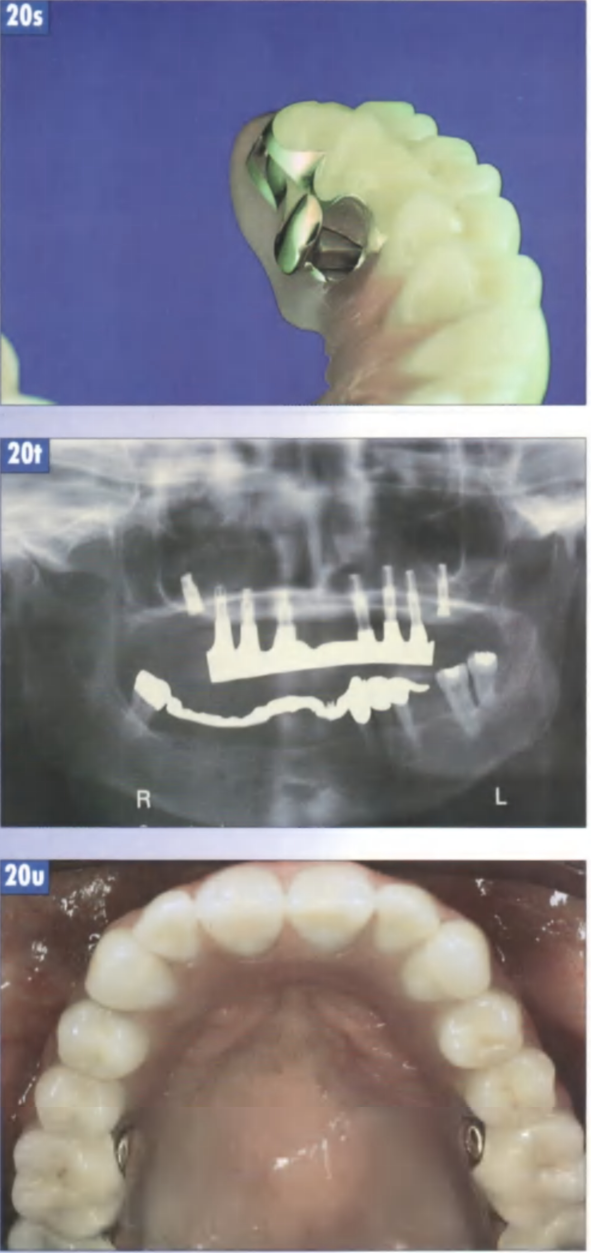

Рис 20г. Готовая первичная балка с промывным каналом: вид со стороны нёбной поверхности.

Рис. 20s. Открывающая головка должна быть легко доступна и открываться до упора без чрезмерных усилий: максимальная амплитуда перемещения составляет порядка 5 мм.

Рис. 20t. Контрольный рентгеновский снимок ситуации после фиксации соединительной балки на верхней челюсти.

Рис. 20и. Готовый протез в полости рта.